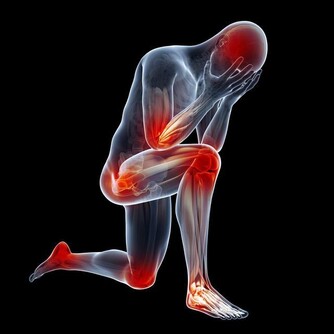

當你保持站立或者坐立的狀態1小時以上的時候,就應該起身活動一下了,沿著房間慢慢溜達一下,通過小腿的肌肉泵作用,使血液回流;另外,工作了一天,晚上回家躺在床上,我建議大家抬高下肢,這樣也是藉助重力的作用,使下肢的血液回流。

此外,給大家推薦幾個預防靜脈曲張的常見動作。在休息的時候,可以做以下的動作,能很好的預防靜脈血栓的形成。

以上方法的核心思想就是收縮小腿肌肉,促進血液回流,如果你有其餘的辦法也能達到這種效果,也可以一試。在這裡,主要是給年輕人們提個醒,如果你現在就發現自己有靜脈曲張,一定要加以重視,及時干預,將肺栓塞的可能性降到最低。